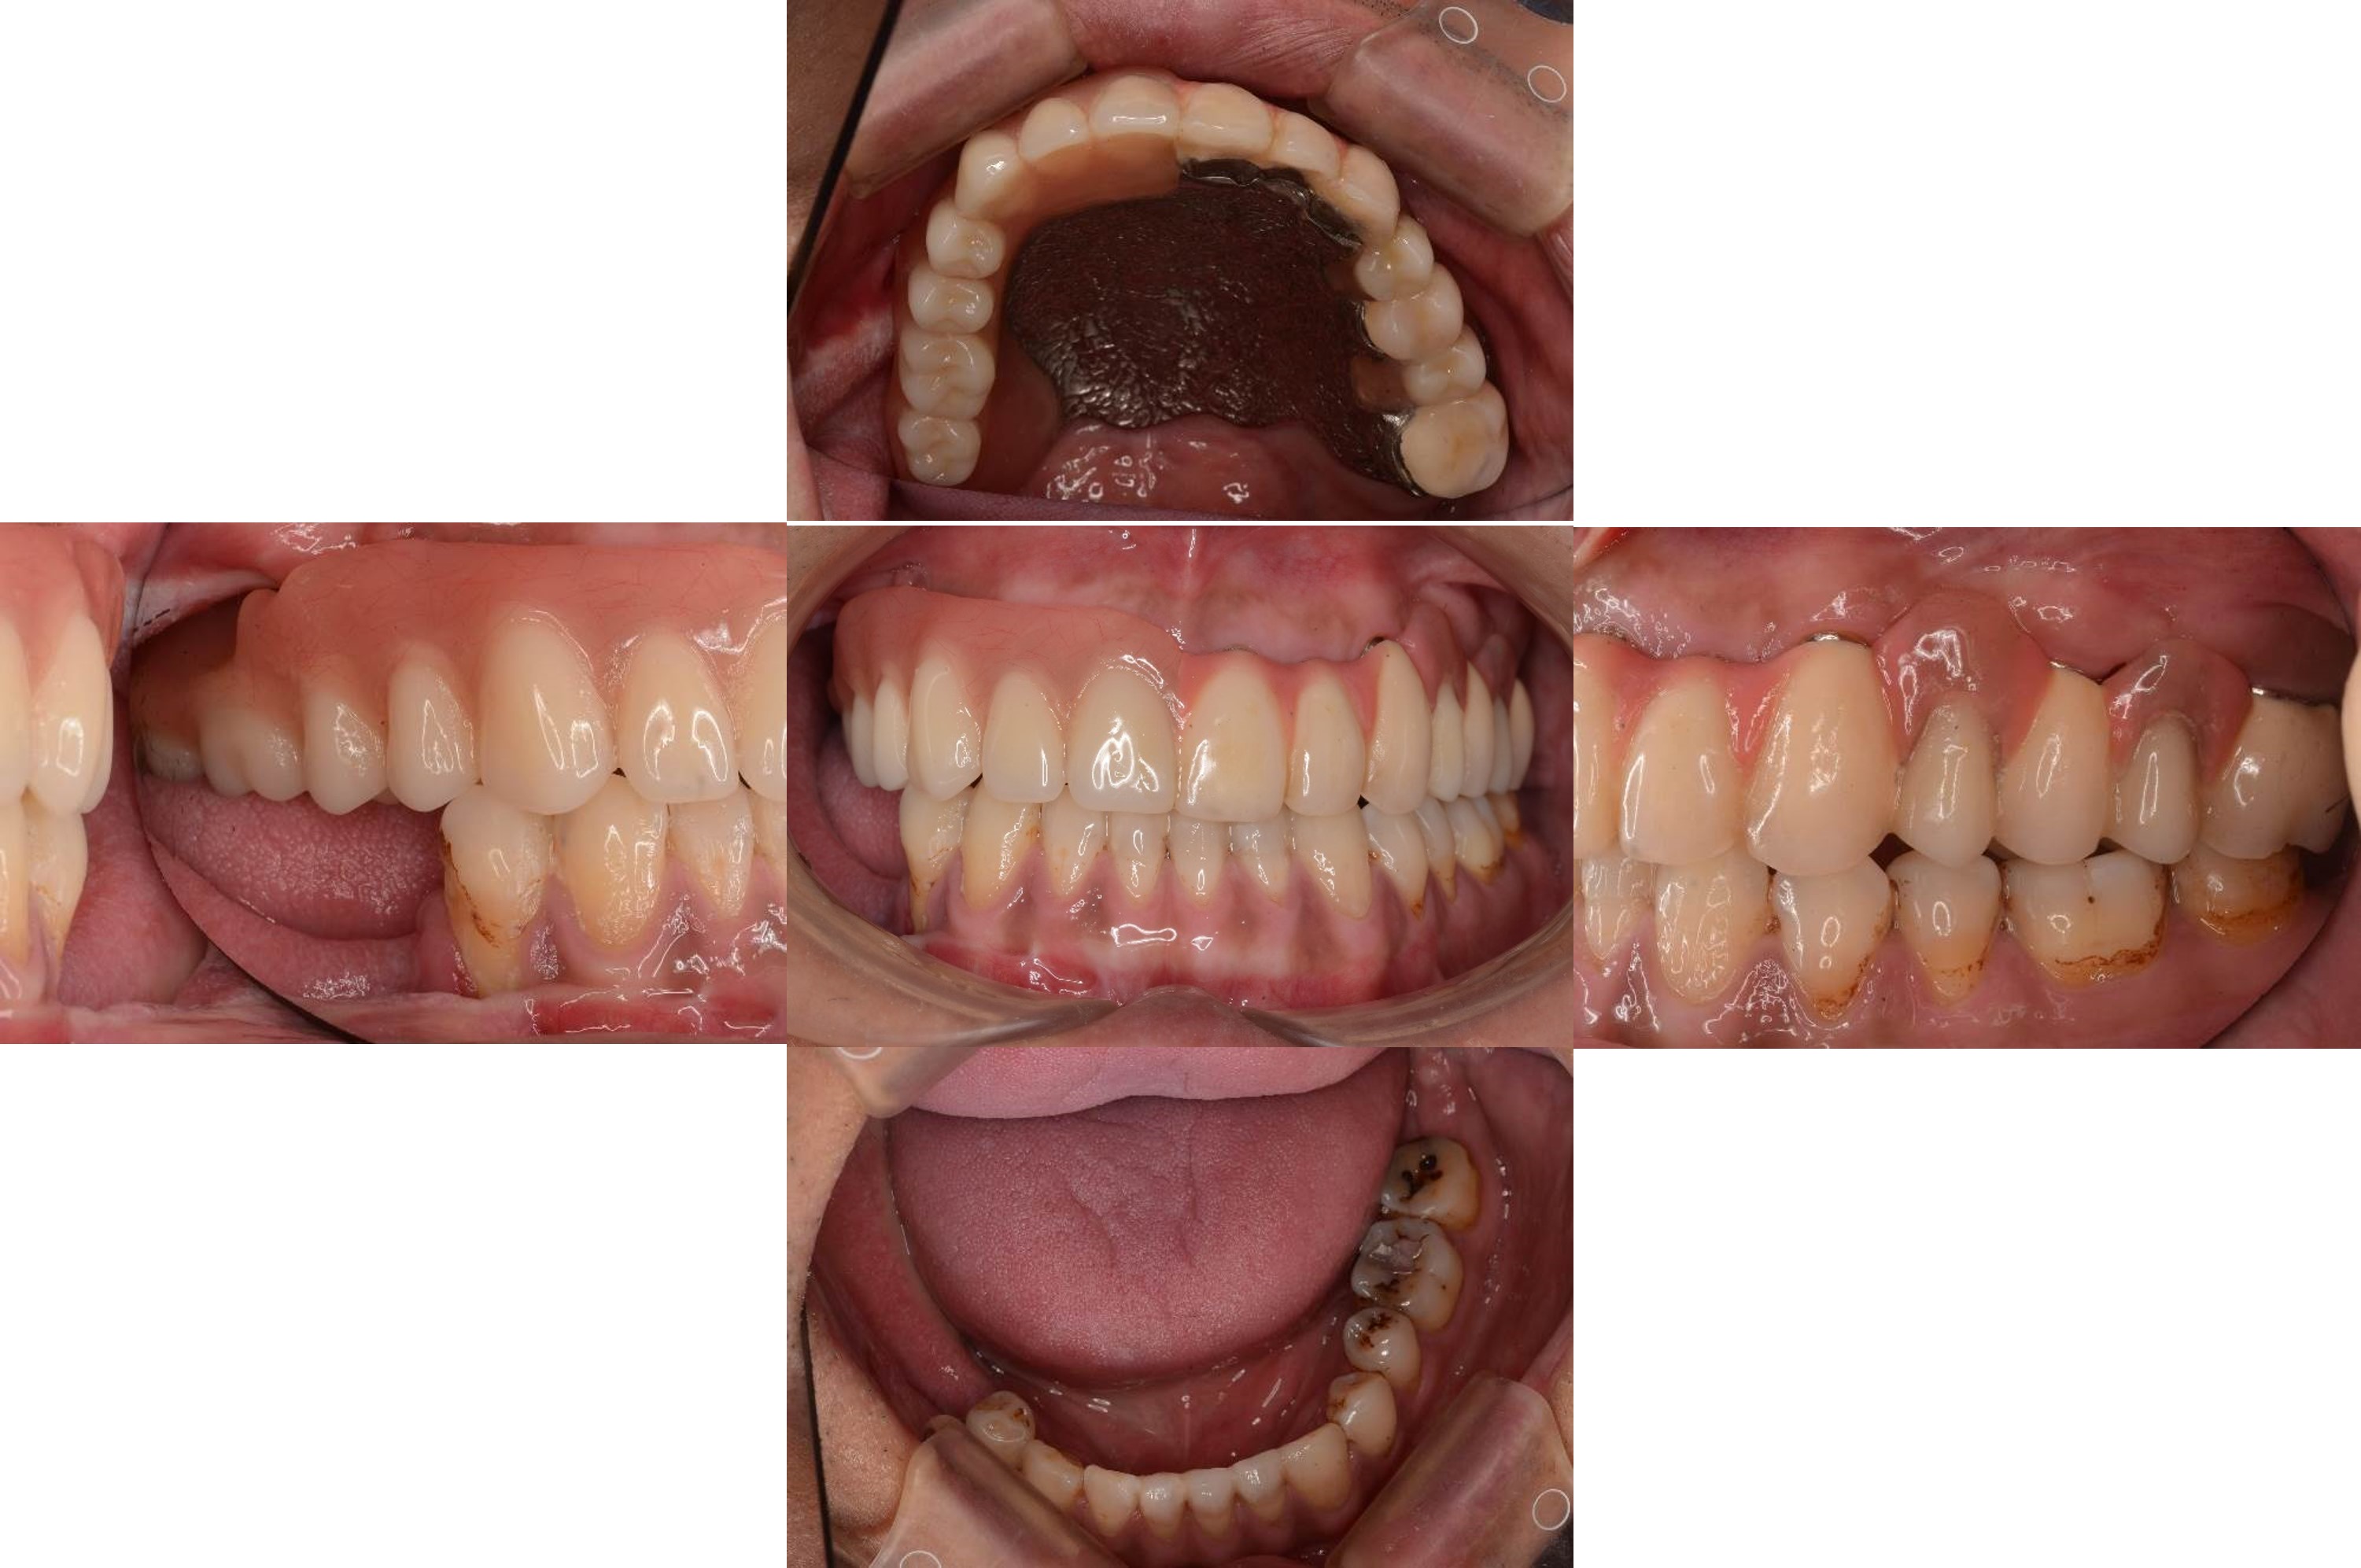

正式假牙完成

口內外冠與活動假牙定位

口內試戴

內冠及定位器口內照

活動假牙口內照

理想咬合支撐

口外支撐性良好

微笑時外形自然